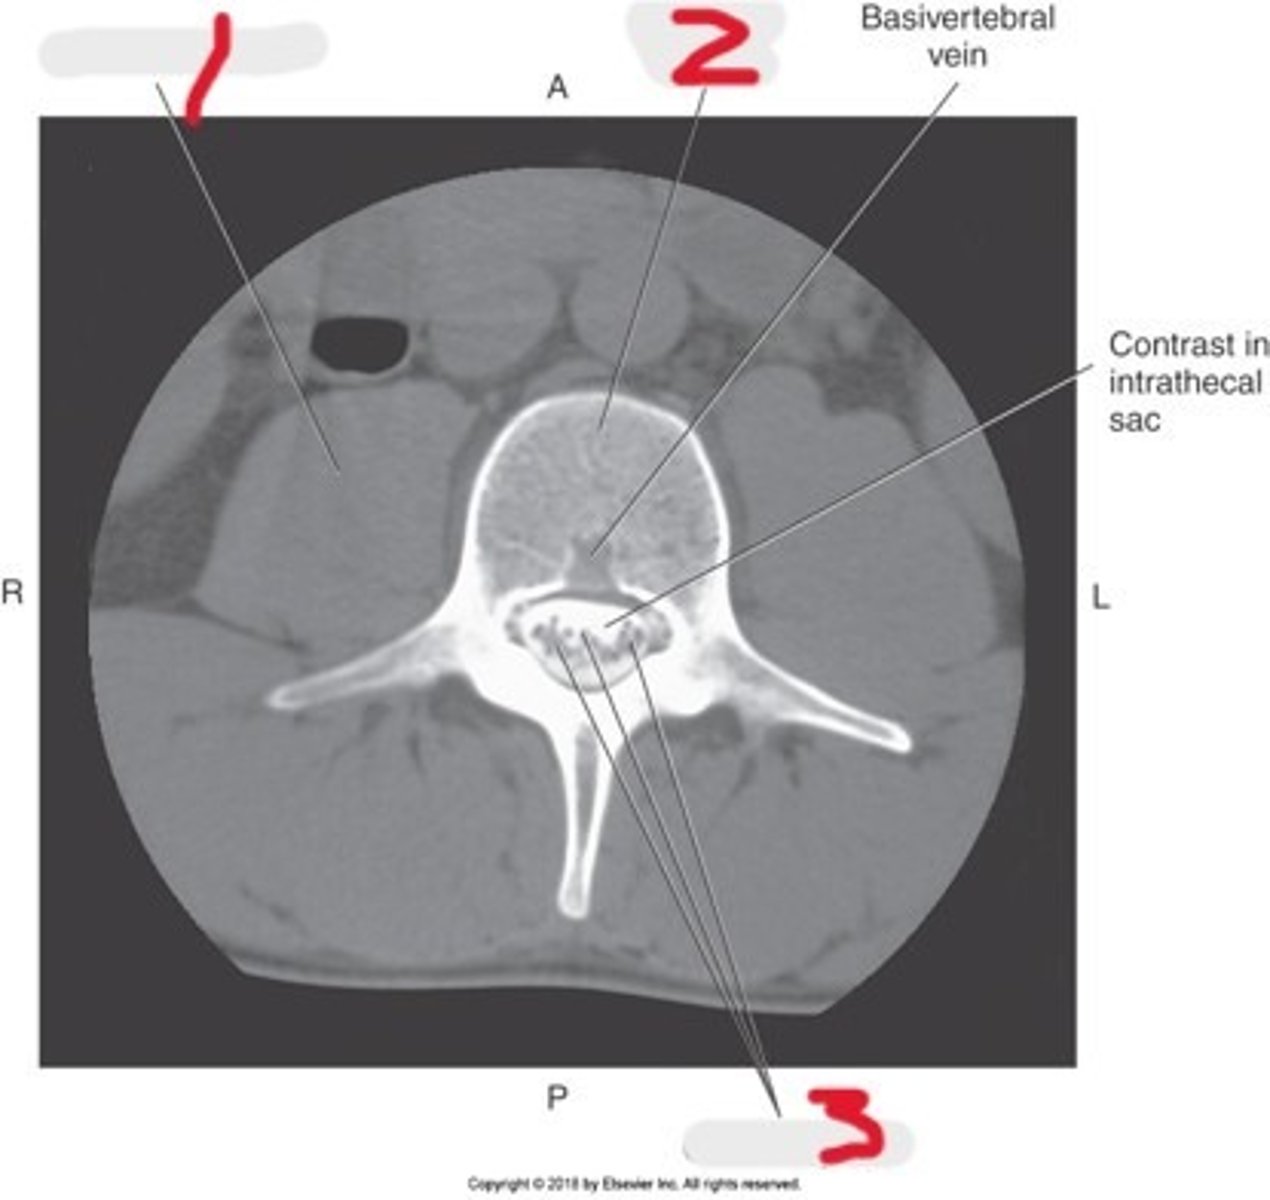

1) Conus medullaris

2) Cauda equina

3) Thecal sac

Name all numbered structures

1) L5

2) Sacrum

3) Conus medullaris

4) Cauda equina

5) Subarachnoid space with contrast

Name all numbered structures